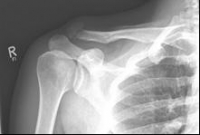

Picture 1                                                                Picture 2

Picture 1: Displaced fracture of the left collarbone before surgery.